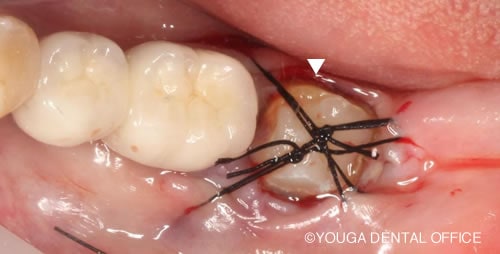

埋伏歯の保存治療ストラテジー 誘導・牽引のタイミングと。埋伏歯の保存治療ストラテジー 誘導・牽引のタイミングと。書籍詳細「埋没歯の保存治療ストラテジー」 | フォルディネット。令和5年 富山県産 赤米 古代米 うるち米 700g -55-。抜歯しない埋伏歯の矯正歯科治療 | 野田 隆夫, 野田 雅代 |本。牽引装置 トラックタイザー ST-5CL|ミナト医科学。埋伏歯の牽引成功、矯正治療終了したSさん」291インビザライン。歯を残したい 抜歯したくない 歯の保存 エクストルージョン。抜歯せずに噛めるようになったエクストリュージョン(牽引)処置。抜歯せずに噛めるようになったエクストリュージョン(牽引)処置。歯を残したい 抜歯したくない 歯の保存 エクストルージョン。抜歯せずに噛めるようになったエクストリュージョン(牽引)処置。歯周再生療法を成功させるテクニックとストラテジー | 宮本 泰和。「埋伏歯の保存治療ストラテジー : 誘導・牽引のタイミングとテクニック」野田 隆夫 / 野田 雅代定価: ¥ 8000#野田隆夫 #野田_隆夫 #野田雅代 #野田_雅代 #本 #自然/医療・薬学・健康